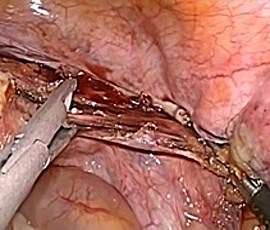

腹腔鏡下胆嚢摘出術の実際

全身麻酔をかけた状態で手術を行います。腹腔鏡下手術では腹部に4カ所の穴、単孔式

腹腔鏡下手術では1カ所の穴を開け、炭酸ガスをおなかの中に入れ、その穴から内視鏡

単孔式腹腔鏡下胆嚢摘出術

腹腔鏡手術で胆嚢の摘出と総胆管結石の摘除を同時に行います。胆嚢摘出後、十二指腸

上部総胆管を切開し、胆道鏡を用いて直視下に胆石を除去します。

採石後は胆道鏡で結石遺残のないことを確認します。その後胆管切開部を腹腔鏡下に

体内で結紮縫合を行い、閉鎖します。